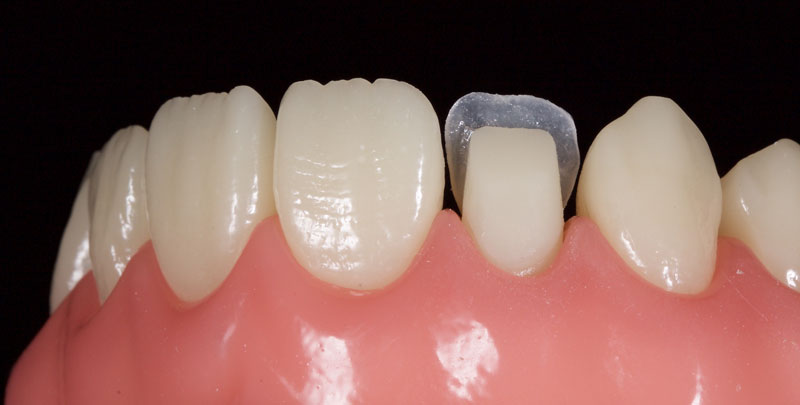

An achromatic enamel shade of low opacity (e.g., GC G-aenial Junior Enamel) is placed on the putty matrix and thinned to a section of 0.1–0.3 mm with an artist’s brush and a modeling resin (e.g., Brush and Sculpt, Cosmedent). This is then adapted to the tooth to form a palatal shell (Fig. 8).